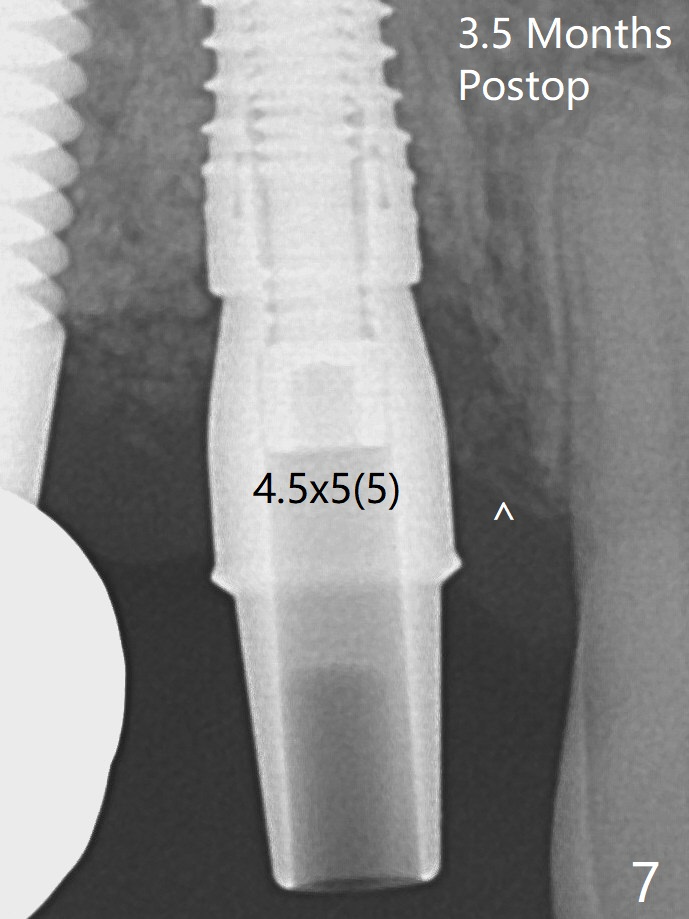

Immediate postop, the abutment margin appears to be subcrestal (biologic width violation, Fig.5).  The gingiva bleeds easily when the provisional is removed 2 weeks and 3.5 months postop.  It is difficult to insert gingival retraction cords.  When an abutment with longer cuff is placed, the packing is easier (Fig.7 (^: resorbed mesial crest)).  *: bone graft.  The mesial socket gap (Fig.5: <) disappears 3.5 months postop (Fig.7).